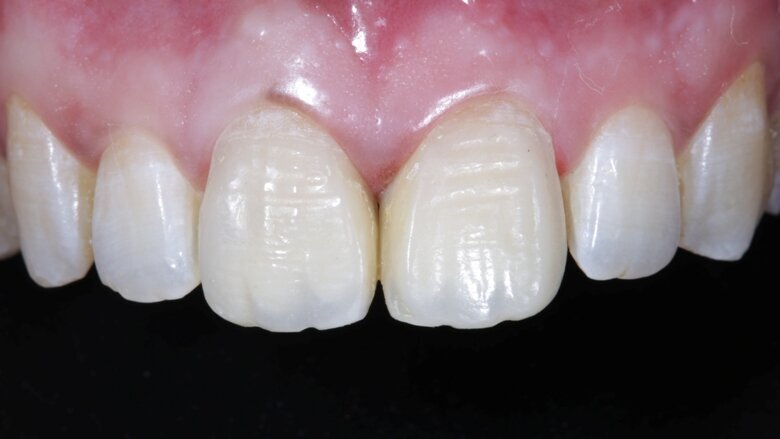

With proper Layering Protocols and systematic finishing and polishing, a direct composite buildup can restore a smile as efficiently as an indirect restoration [ Fig 18, 19, 20 ]

Fig 18 After 48 hours of rehydration